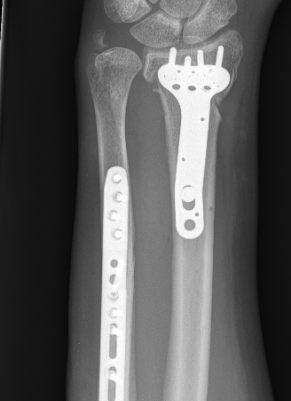

Distal radial osteotomy & ulnar shortening

Indications

Unacceptable radial alignment

DRUJ not reduced by radius osteotomy

DRUJ articular surface acceptable

Distal radial osteotomy & ulnar resection / fusion

DRUJ articular surface unacceptable